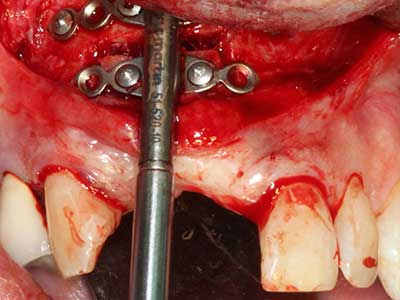

Piezosurgery has additional advantages when harvesting bone blocks. In addition to the high precision with osteotomy described above, the use of the thin saw tips specifically minimizes loss of material. Greater loss of material during harvesting can be expected with the thicker instrument tips, particularly when using Lindemann drills (Lakshmiganthan, Gokulanathan et al. 2012). The basal separation, which is necessary particularly for retromolar block transplants, is simplified by specially designed rectangular saws, with the result that piezosurgery is viewed as a precise, simple and safe procedure for harvesting retromolar bone blocks (Happe 2007) (Fig. 1-12).